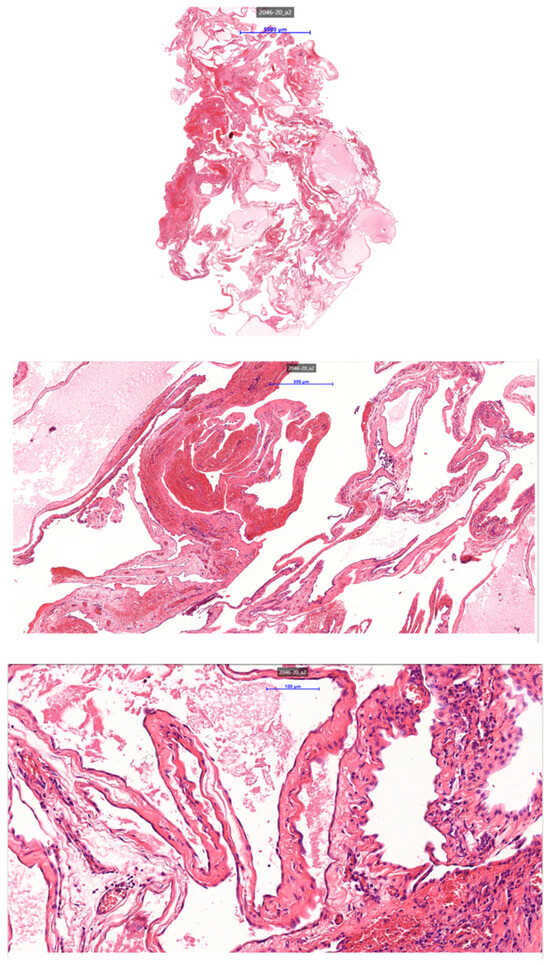

A Rare Case of Multilocular Mesothelial Inclusion Cysts of the Pericardium: Diagnosis, Treatment, Follow Up, with Comprehensive Review of the Literature

by Ali Shadmanian, Kosha Patel, Endre Alács, Henriette Gavallér, Szilva Agocs and Miklós Bitay

Background: Multilocular mesothelial inclusion cysts—also known as benign multicystic mesothelioma (BMM)—are rare, typically arising in the peritoneal cavity. Pericardial involvement is extremely uncommon and can pose diagnostic and therapeutic challenges due to their recurrent and infiltrative nature. Accurate diagnosis and surgical strategy are [...] Read more.

Background: Multilocular mesothelial inclusion cysts—also known as benign multicystic mesothelioma (BMM)—are rare, typically arising in the peritoneal cavity. Pericardial involvement is extremely uncommon and can pose diagnostic and therapeutic challenges due to their recurrent and infiltrative nature. Accurate diagnosis and surgical strategy are critical for management and recurrence prevention. Methods: We present the case of a 36-year-old woman with a prior history of malignant melanoma who developed recurrent multilocular cystic masses of the pericardium. Initial imaging with echocardiography, cardiac magnetic resonance (CMR), and computed tomography (CT) revealed multilocular pericardial cysts. Surgical resection was performed under cardiopulmonary bypass (CPB), but complete excision was limited due to epicardial infiltration. Histopathology confirmed a benign mesothelial origin. One year later, recurrence prompted a second surgical intervention with total pericardiectomy and Gore-Tex patch reconstruction. Results: Postoperative recovery was uneventful in both instances. Follow-up imaging at 6 and 12 months demonstrated no significant recurrence. Histological analysis confirmed benign cysts lined with mesothelial cells, positive for calretinin and WT-1. This represents one of the first documented living cases of pericardial BMM managed with staged surgery and total pericardiectomy. Conclusions: Pericardial BMM is a rare, benign, but potentially recurrent lesion. In cases of extensive or recurrent disease, total pericardiectomy may offer definitive treatment. Multimodal imaging, histopathological evaluation, and personalized surgical planning are essential for effective management. Full article

Figure 1